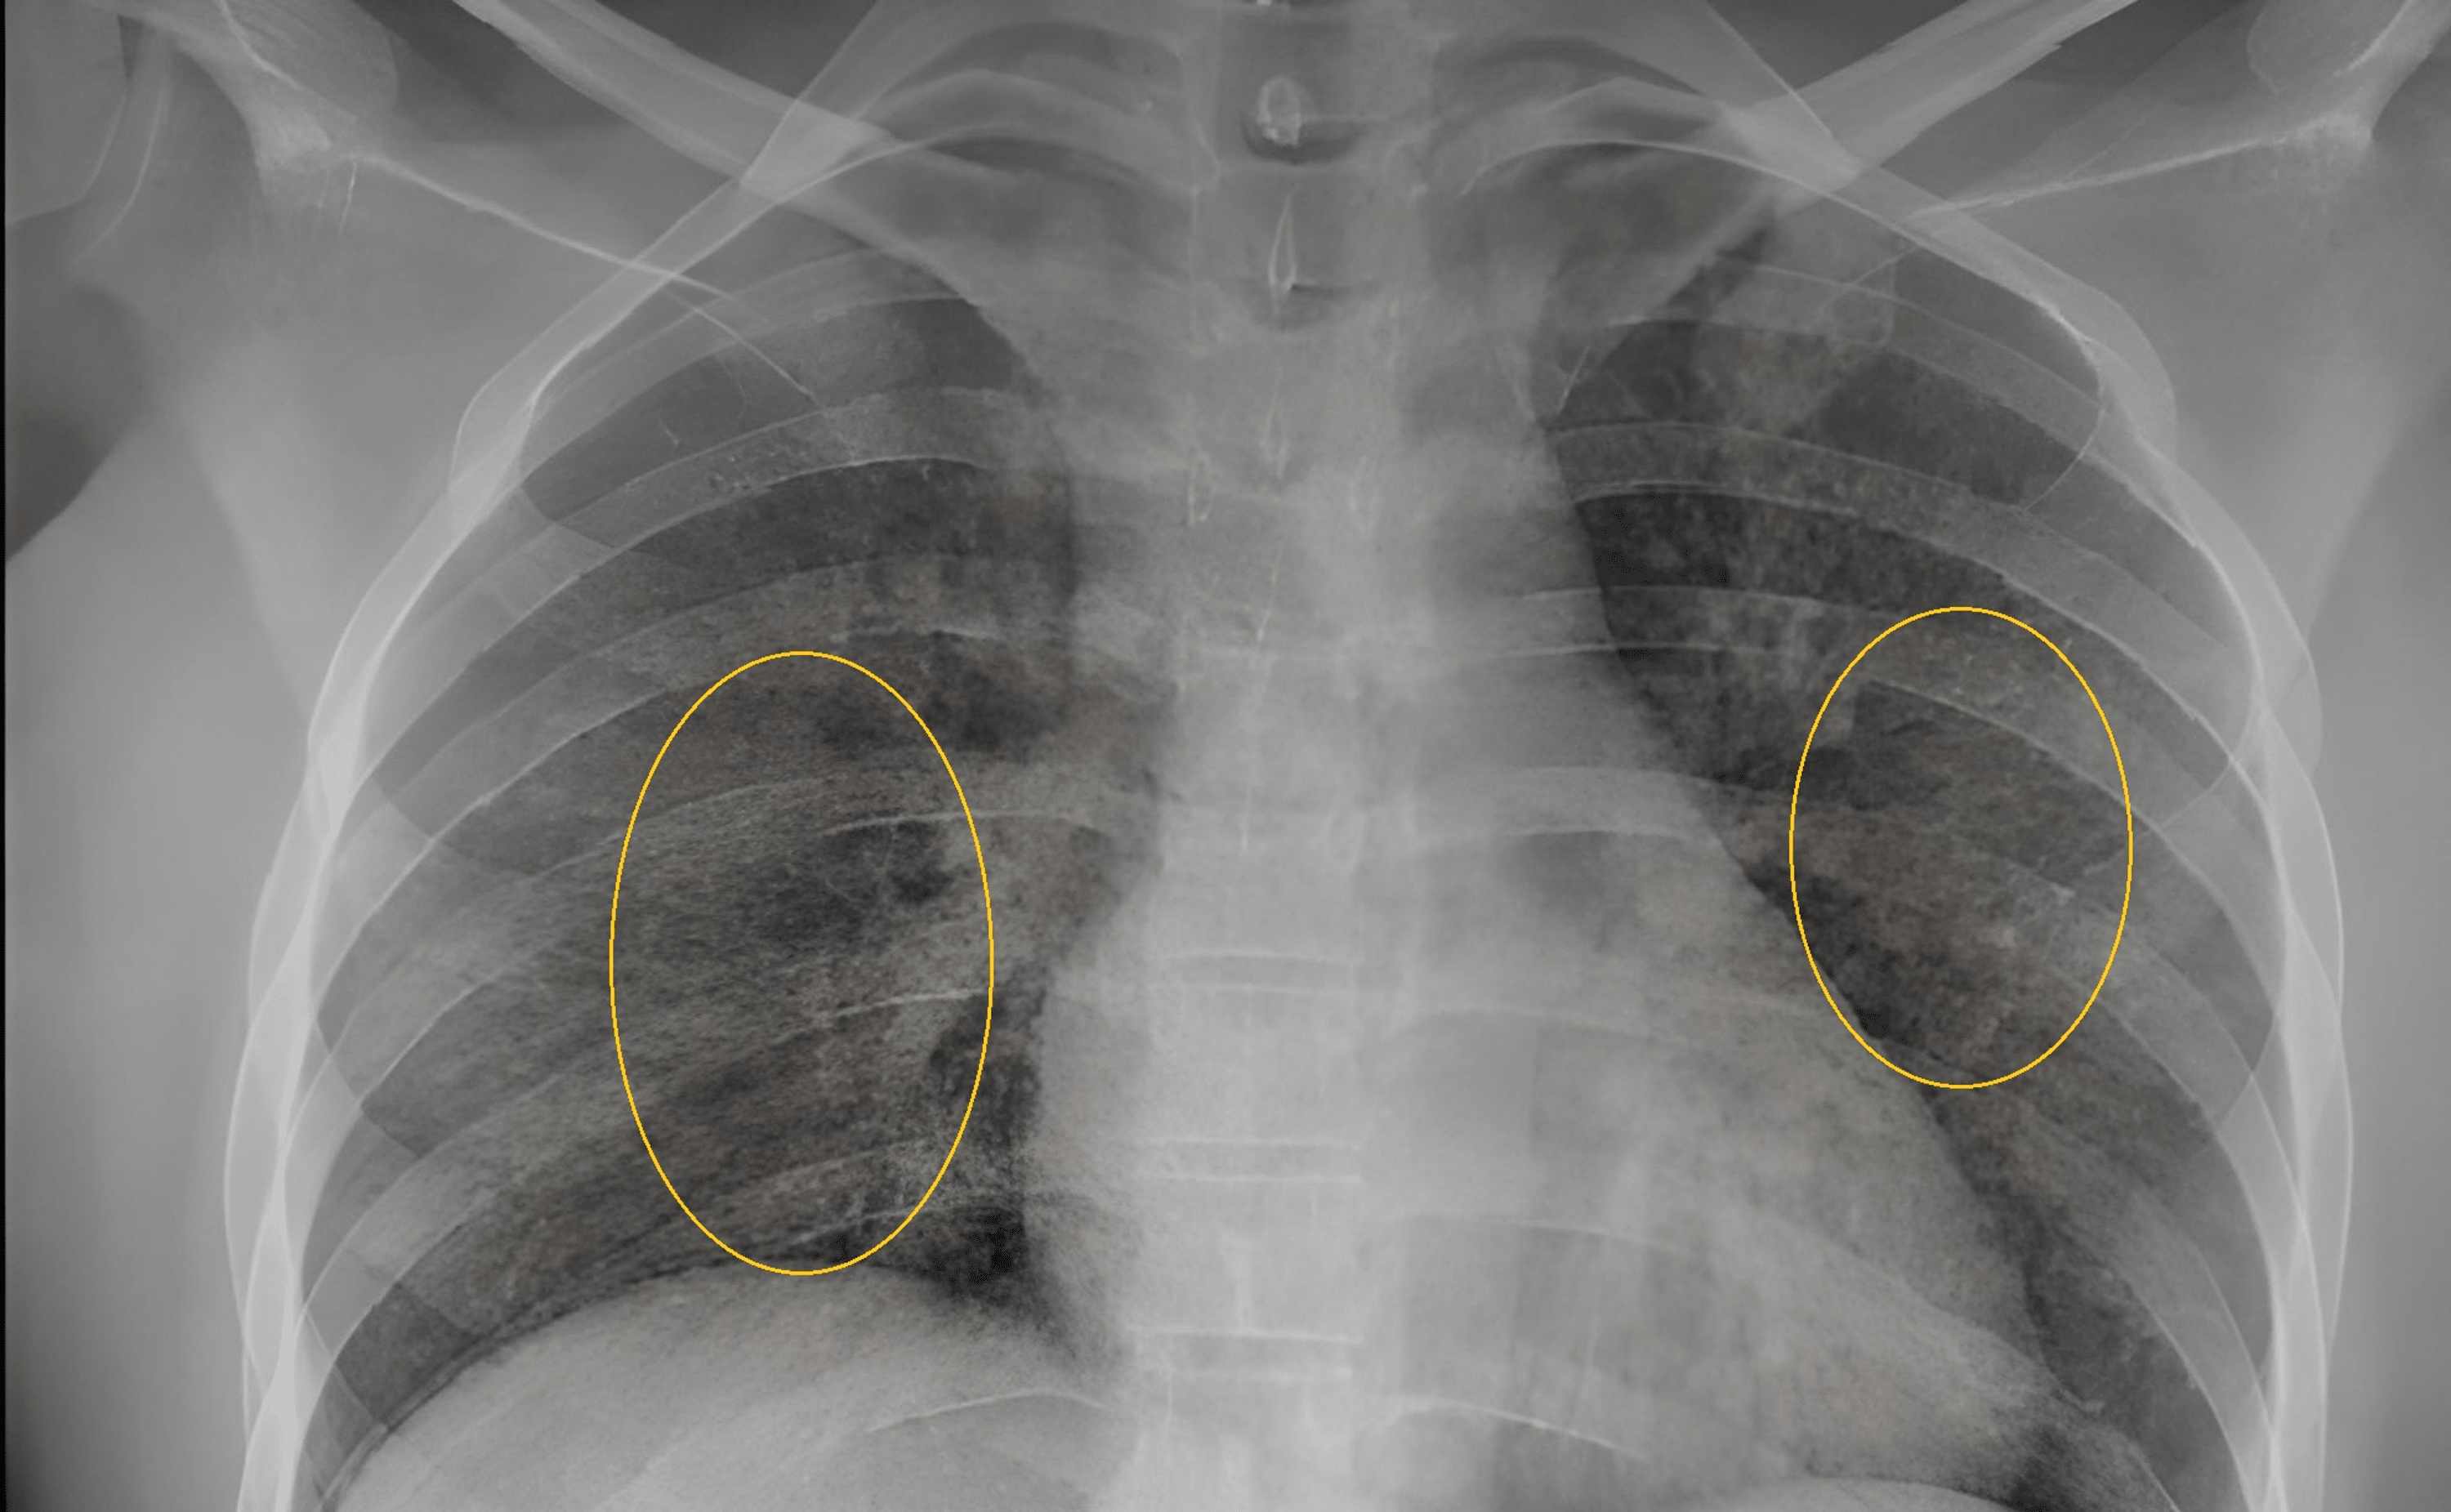

From www.researchgate.net

Chest Xray showing multiple bilateral lungs patches with the Miliary Chest X-Ray Differential Diagnosis In selected cases the distribution of. The differential diagnosis of miliary pattern on chest radiography includes miliary tuberculosis (tb), histoplasmosis, sarcoidosis,. The differential diagnosis of miliary pattern on chest radiography includes miliary tuberculosis (tb), histoplasmosis, sarcoidosis, pneumoconiosis, bronchoalveolar carcinoma,. Miliary nodules can be the manifestation of multiple diseases and the differential diagnosis is broad once. Histological confirmation of the diagnosis. Miliary Chest X-Ray Differential Diagnosis.